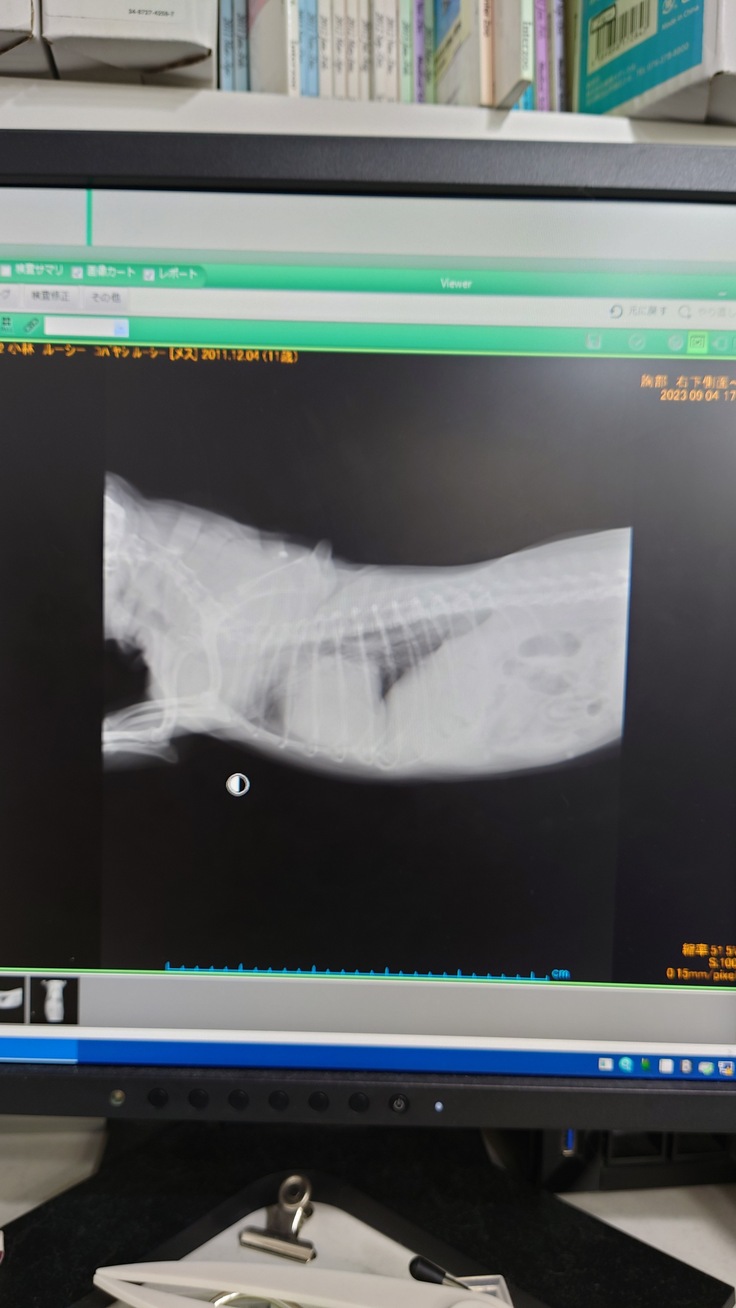

すぐにレントゲンを撮って肺の状態を確認しました。

五日前のレントゲンよりも肺の水の量が増してしまっていたようで

呼吸が荒くなっていたようです。

ギリギリ肺水腫にならなかった、状態とのことだそうです。